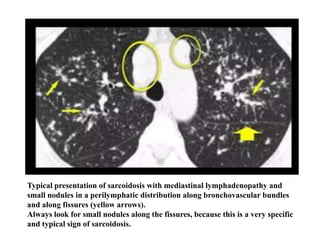

HRCT findings in Sarcoidosis

• Common findings:

-Small nodules in a per lymphatic distribution

(i.e. along subpleural surface and fissures, along

interlobular septa and the peribronchovascular

bundle).

-Upper and middle zone predominance.

-Lymphadenopathy in left hilus, right hilus and

paratracheal (1-2- 3 sign). Often with

calcifications.

Typical presentation of sarcoidosis with mediastinal lymphadenopathy and

small nodules in a perilymphatic distribution along bronchovascular bundles

and along fissures (yellow arrows).

Always look for small nodules along the fissures, because this is a very specific

and typical sign of sarcoidosis.